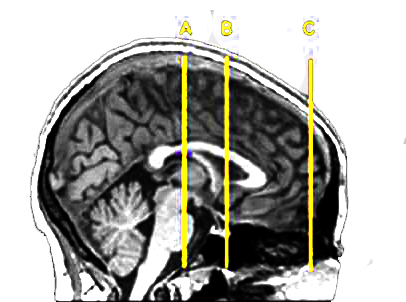

In some experiments, Kuhnen puts people inside fMRI machines, gives them investments to choose from, and sees which areas of the brain light up. She also looks at their genes, their personalities, and their credit reports.